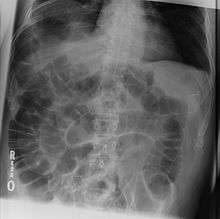

The dark areas on both sides of the intestines indicate that air is present in both sides. This is called "Rigler's sign".

- Rigler's sign